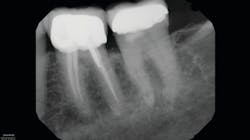

As a clinic based heavily on referrals, we get CBCT studies from other clinicians who invariably have used much larger FOVs than are needed. In endodontics, for example, dual-arch or larger studies expose patients to significantly more radiation and increased interpretation time—often at the expense of resolution for the areas of interest and imaging needs. This is likely done to reduce the chance of retakes due to poor alignment with systems that either don’t have scouting capability or only have it in a single plane.

With the CS 9600’s optional SmartAuto 3-D and 2-D scouts, structures of interest can be confirmed in the FOV, and the center of rotation is adjusted to optimize the ensuing study. In the past, and with extraoral systems that don’t have multiplanar scouting, retakes were not uncommon. Now, the ability to hit the target 100% of the time has allowed us to routinely use the smallest FOV (4 x 4 cm), which reduces the dose of radiation for patients.

In more dense anatomic areas, more subtle radiographic findings that are not appreciated with projection radiography are visible in a passing glance with CBCT. Advanced imaging also helps with treatment planning and image-guided treatment (IGT). IGT, particularly in endodontics, allows a better estimation of the anatomic complexity and possible strategies for managing it. This also facilitates planned endodontic access to minimize the amount of sound tooth structure that is removed and maximize the remaining dentin.